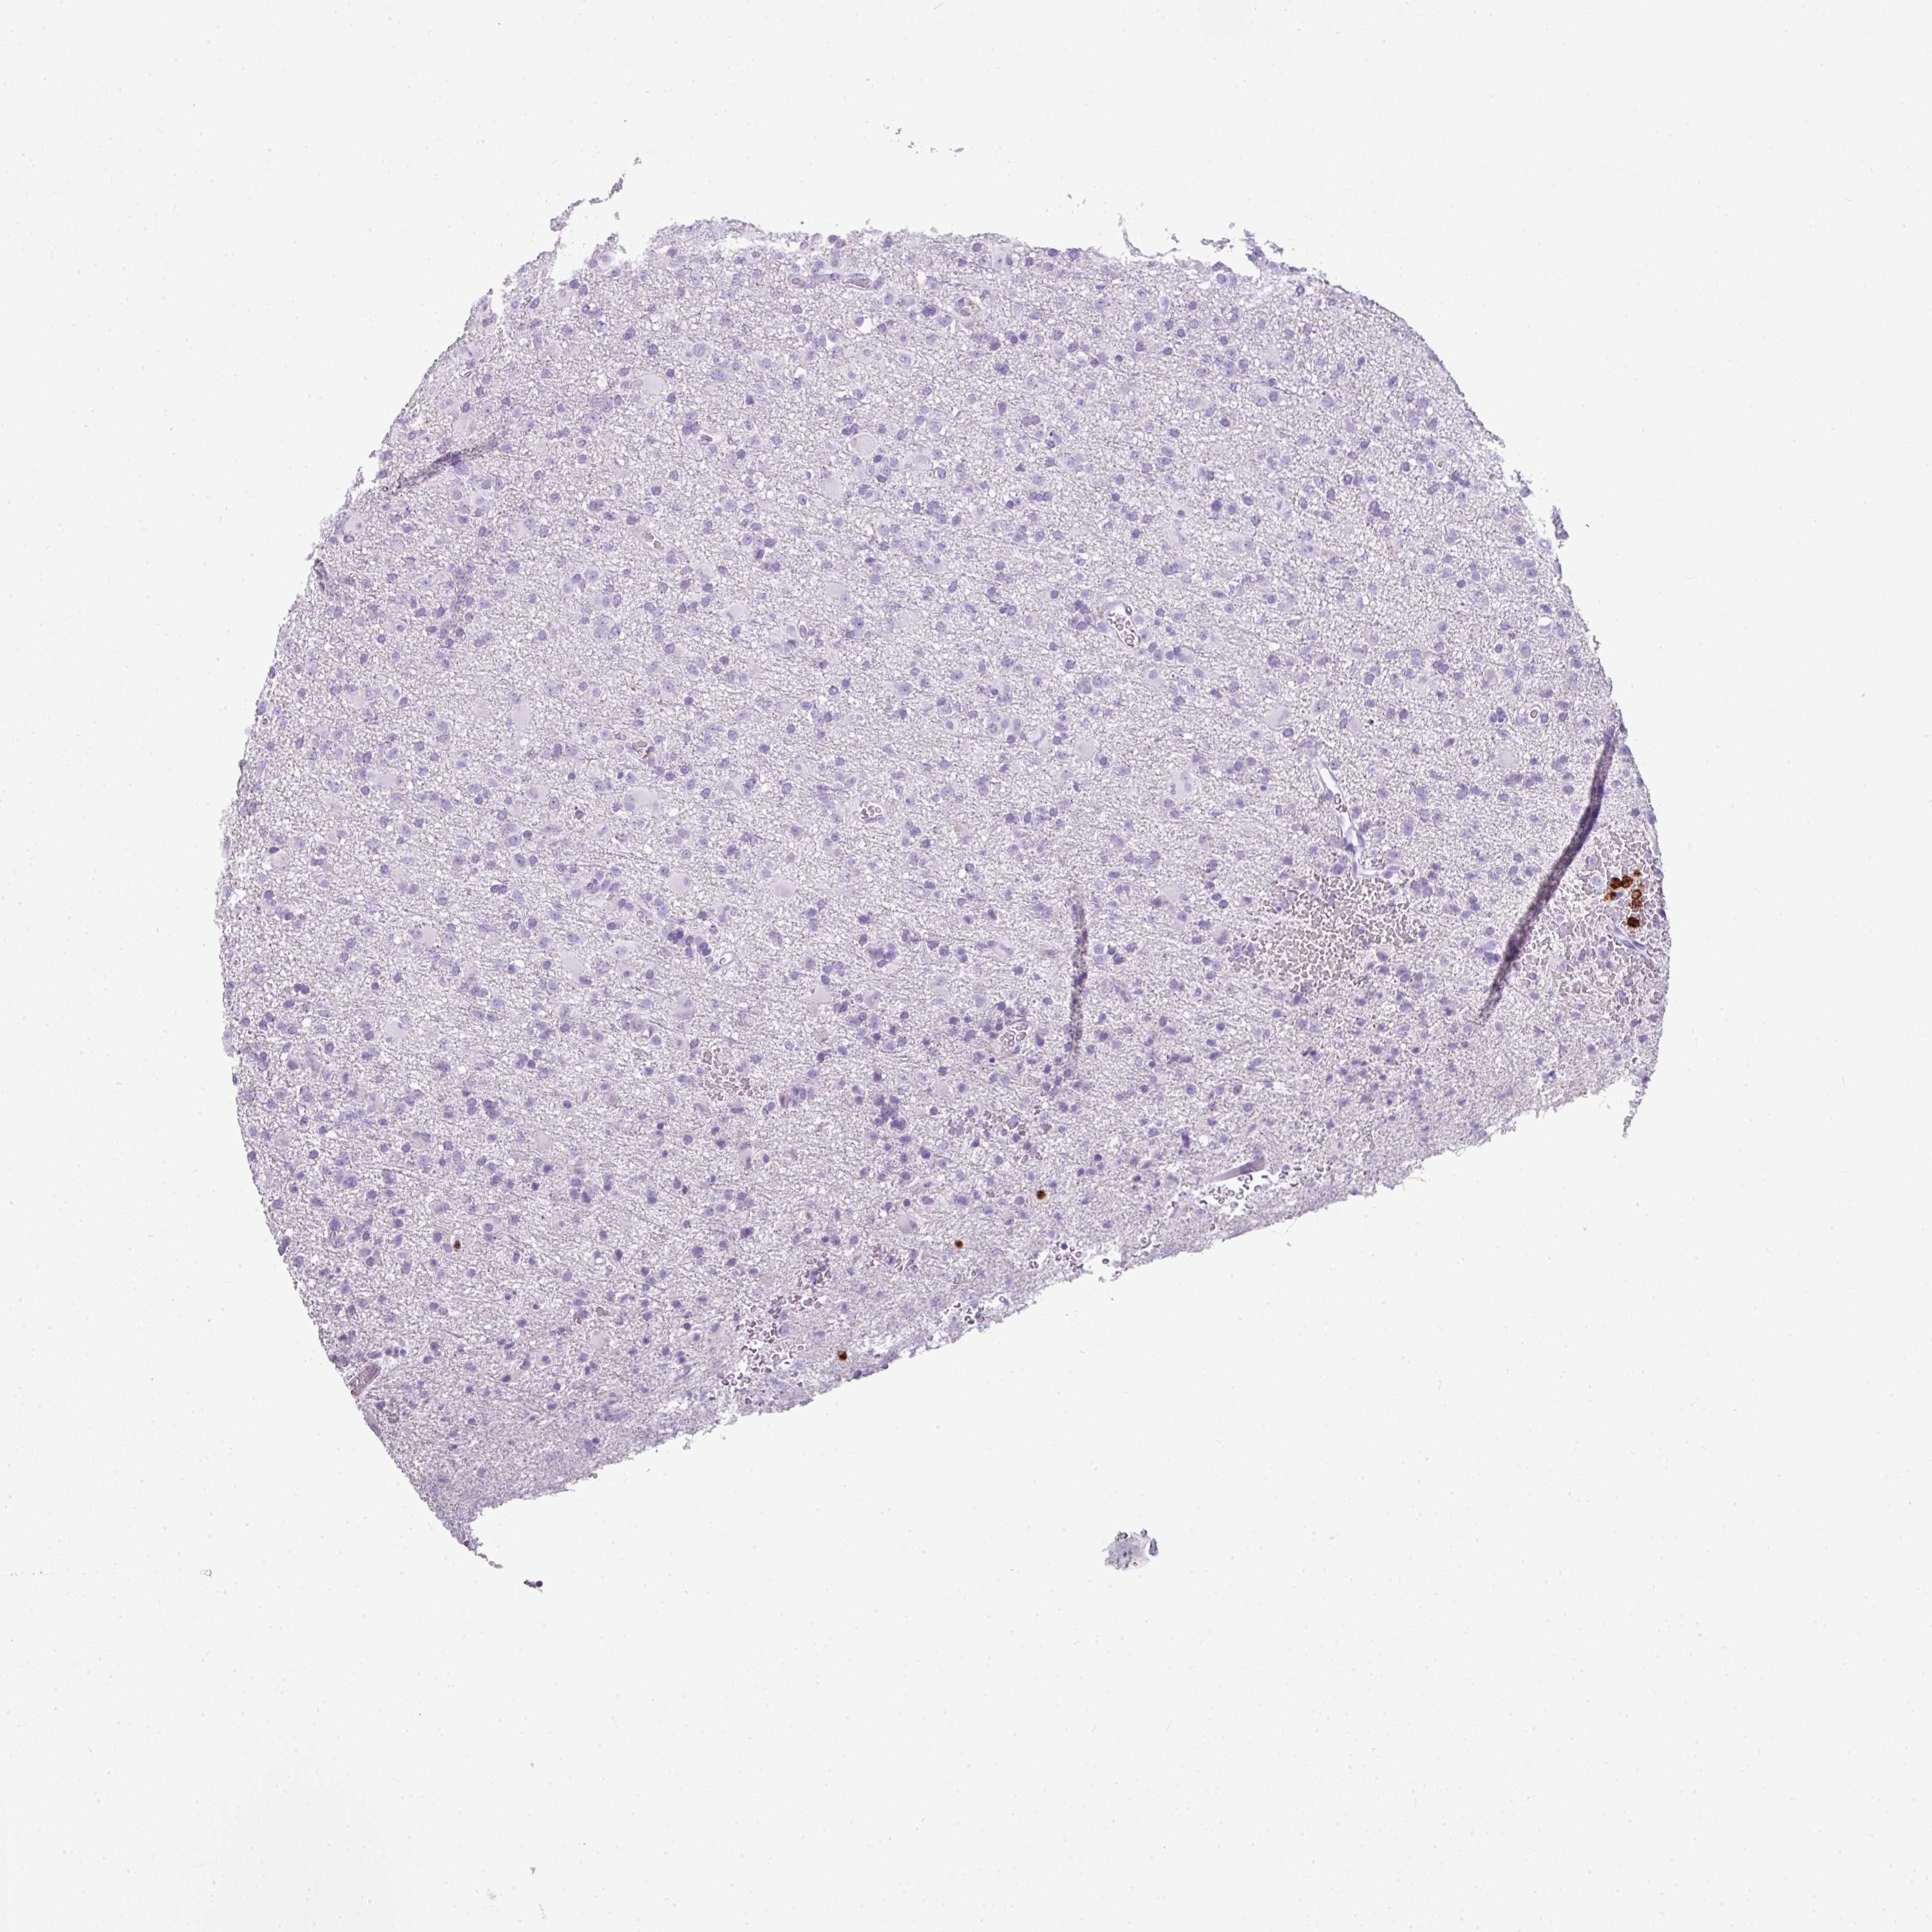

GLIOMA - Protein expressioni

A mouse-over function shows sample information and annotation data. Click on an image to view it in a full screen mode. Samples can be filtered based on level of antibody staining by selecting one or several of the following categories: high, medium, low and not detected. The assay and annotation is described here.

Antibody stainingi

Antibody staining in the annotated cell types in the current human tissue is reported as not detected, low, medium, or high, based on conventional immunohistochemistry profiling in selected tissues. This score is based on the combination of the staining intensity and fraction of stained cells.

Each image is clickable and will lead to virtual microscopy that enables deeper exploration of all samples and also displays staining intensity scores, fraction scores and subcellular localization as well as patient and tissue information for each sample.

Antibody HPA047737

Antibody CAB000110

Staining

High

Medium

Low

Not detected

Intensity

Strong

Moderate

Weak

Negative

Quantity

>75%

75%-25%

<25%

None

Location

Nuclear

Cytoplasmic/membranous

Cytoplasmic/membranous,nuclear

Glioma, malignant, High grade

Glioma, malignant, Low grade